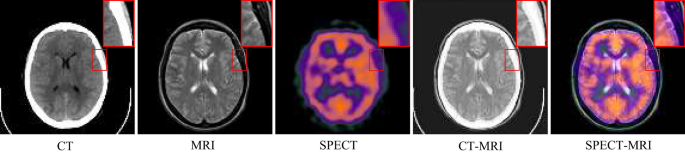

In clinical practice, image scans are essential screening methods to obtain the imaging characteristics of the diseased tissue. For instance, single-photon emission computed tomography (SPECT) effectively detects the activity and metabolic strength of human tissue cells by injecting a radioactive tracer into the patient’s body and analyzing the emitted light. Another well-known technique is magnetic resonance imaging (MRI), which uses electromagnetic waves to characterize the soft tissues of the body. For tissues and organs with higher density, such as bones, computed tomography (CT) is commonly used. CT employs a narrow beam of X-rays to generate cross-sectional images of the body (slices) at a specific thickness. Unfortunately, each of these imaging techniques has its limitations when used independently. SPECT monitors the metabolic activity of tissue cells but provides blurred images, often losing information about tissue structure. Magnetic resonance imaging captures soft tissues, particularly in the brain, with high resolution, but lacks detailed information about the skeleton. CT enhances the details of high-density tissues compared to MRI, but soft tissues are displayed at a lower resolution. These limitations make it tedious and time-consuming for clinicians to switch between different imaging modalities to obtain more comprehensive patient information. As shown in Fig. 1, multi-modal medical image fusion combines complementary information from multiple modalities to create a single image with richer details, providing clinicians with a more accurate imaging basis for patient diagnosis and treatment1,2. This technology is widely applied in intraoperative navigation3, tumor segmentation4 and adjuvant radiotherapy5.

Schematic of multimodal medical image fusion.